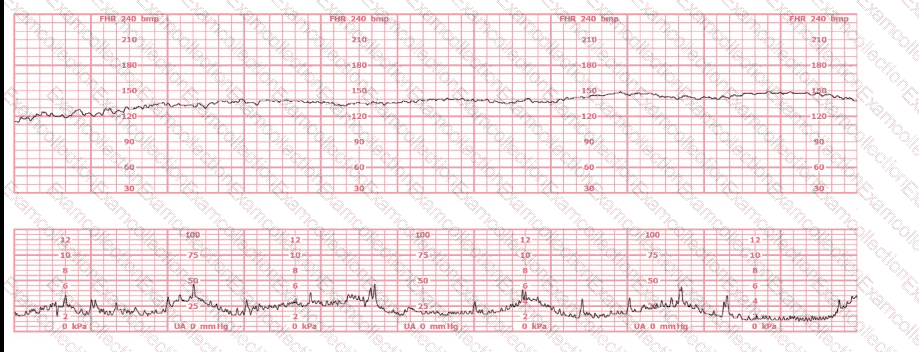

A woman (G1, P0) at 41-weeks gestation presents to OB triage to rule out labor. Her cervical exam is 1 cm/50%/-2. Membranes are intact. She would like to go home if not in labor. Based on this tracing, which represents the last two hours, the best approach is: